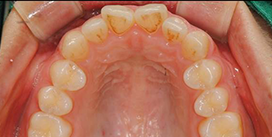

실제 치료 사례

데이몬 교정으로 완성된 아름다운 변화를 확인하세요

비발치 데이몬 교정

치아를 뽑지 않고도 완벽한 치열 개선